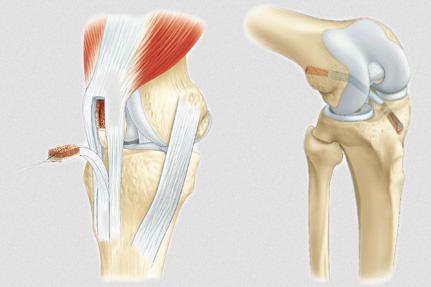

Le ligament croisé antérieur (LCA) est une des structures clés garantissant la stabilité genou lors des activités sportives. Au football, la fréquence des contacts, les accélérations brutales et la nécessité de pivoter rapidement exposent particulièrement ce ligament aux contraintes mécaniques sévères. L’une des causes principales de blessure au football reste l’entorse genou, souvent accompagnée d’une déchirure partielle ou complète du ligament croisé.

Pour les déchirures complètes du ligament croisé antérieur, la chirurgie ligament est souvent préconisée pour restaurer la stabilité du genou, notamment chez les sportifs désirant reprendre une activité intense et compétitive. Cette opération consiste généralement en une reconstruction ligamentaire par greffe, souvent prélevée sur le tendon du joueur lui-même. Elle est suivie d’une phase longue de rééducation fonctionnelle, indispensable pour optimiser la récupération.